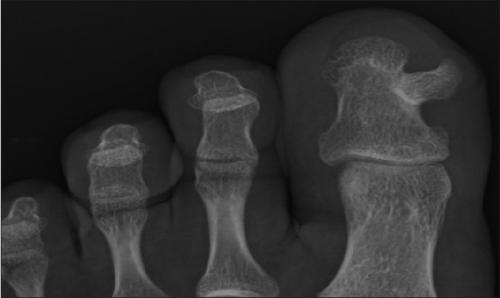

Чаще всего наблюдается экзостоз большого пальца ноги. Это может сопровождаться вальгусной деформацией этого пальца, что проявляется его отклонением от нормальной оси в сторону соседних пальцев. В результате могут деформироваться и 2—3 пальцы стопы, приобретая молоткообразную форму.